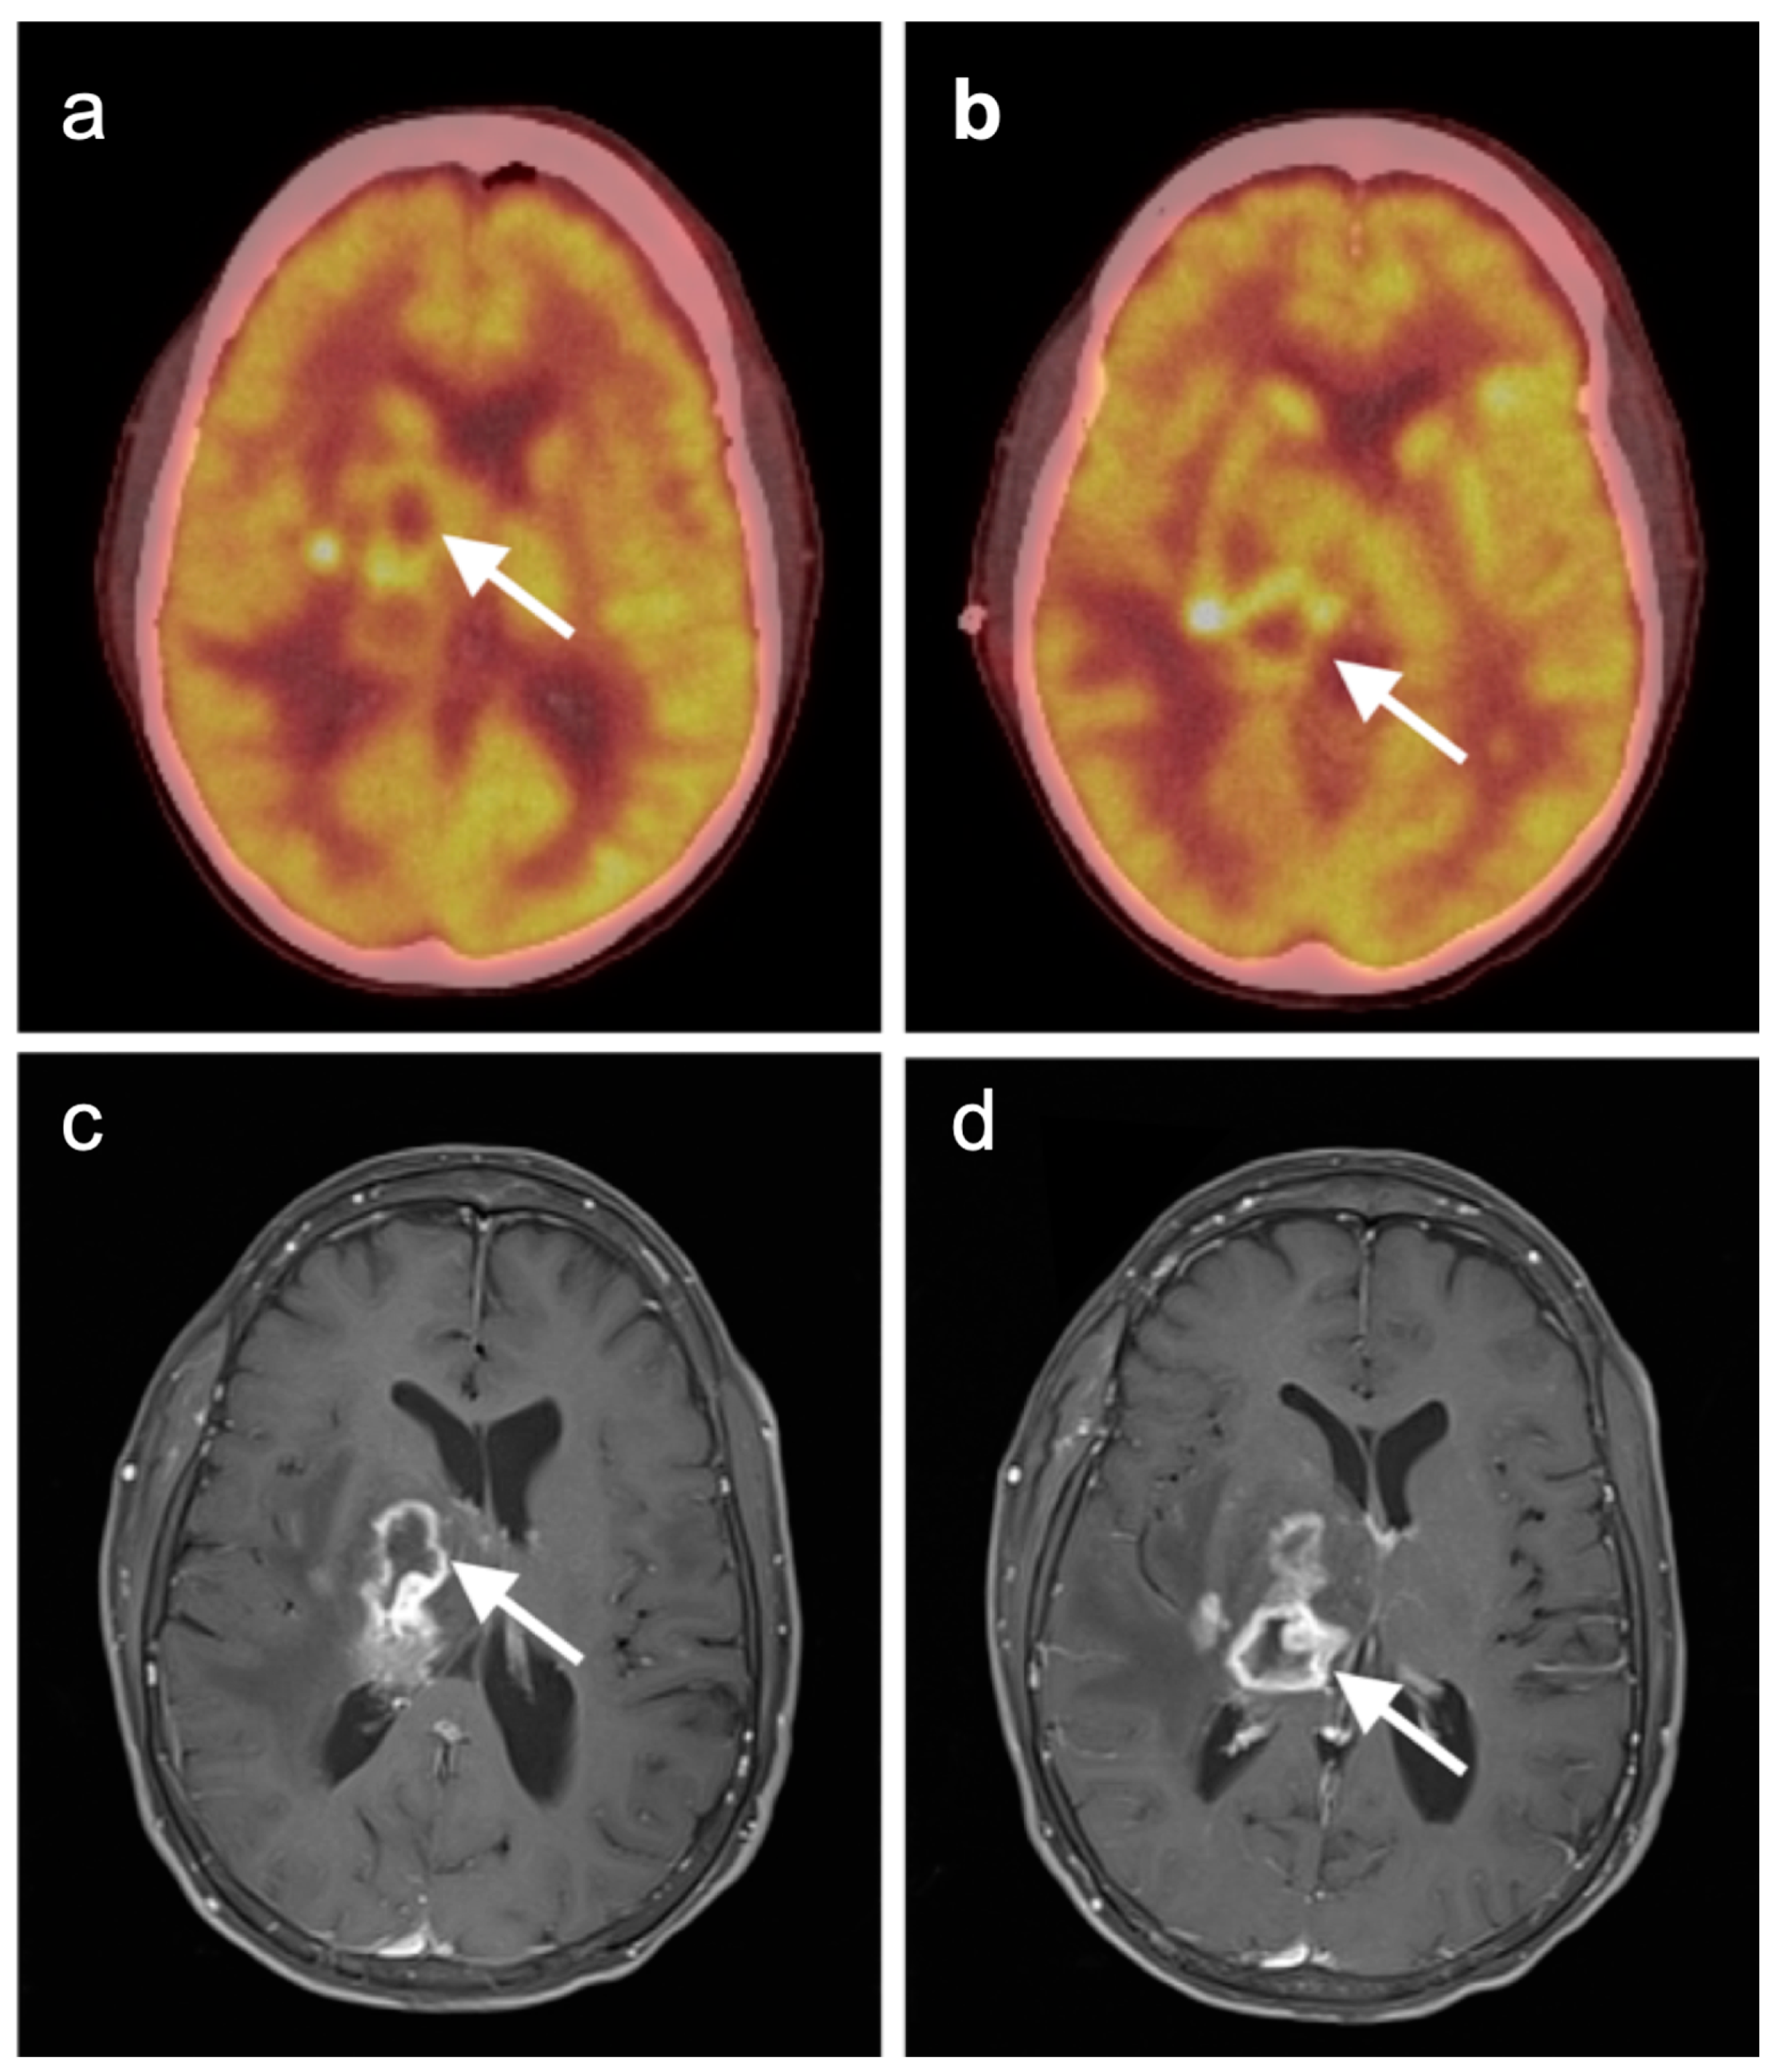

3.6. Response to Therapy

4. Conclusions